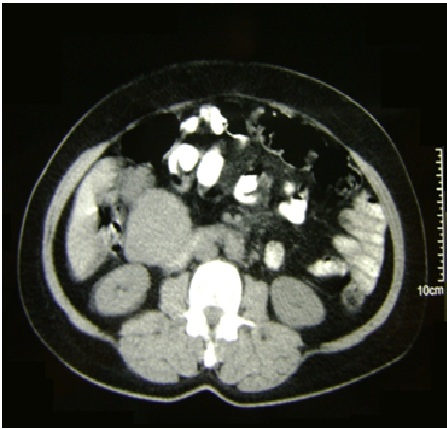

Os tumores estromais gastrointestinais (GISTs) são os tumores mesenquimais mais frequentes do tubo digestivo. São tumores originários das Células Intersticiais de Cajal. Podem acometer qualquer segmento gastrointestinal, predominando no estômago e jejuno, porém no duodeno é uma localização rara, ocorrendo em torno de 3% a 5% dos pacientes acometidos por GIST. Entre 10% a 30% são completamente assintomáticos, sendo descobertos acidentalmente durante endoscopia, diagnósticos radiológicos e até durante intervenções cirúrgicas devido a várias razões. Se presente, os sintomas clínicos são inespecíficos e incluem: cólica abdominal, sensação de saciedade precoce, flatulência, prolongado sangramento gastrointestinal, anemia de origem desconhecida, perda de peso, vômitos e abdômen agudo. Na tomografia computadorizada, que é considerada como técnica de referência, os GISTs se apresentam tipicamente como massas grandes, bem delimitadas, heterogêneas e, às vezes, exofíticas. Para o seu tratamento, preconiza-se a exérese cirúrgica.